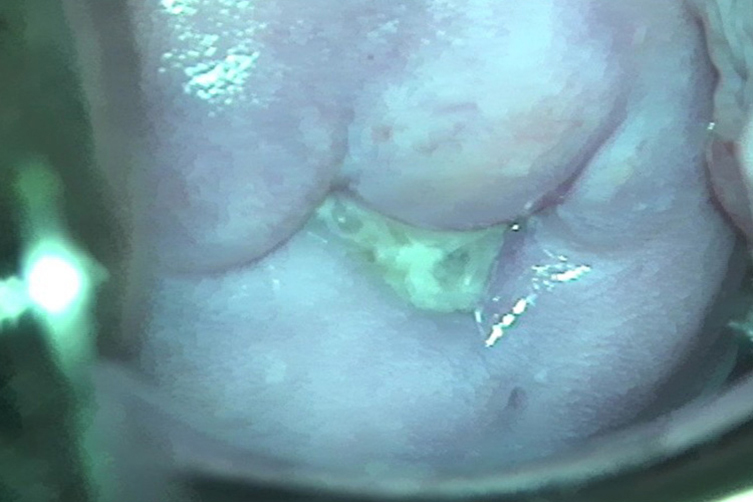

宫颈为最常见发病部位,可表现为阴道分泌物增加,妇科检查可见分泌物为脓性,呈黄色可覆盖宫颈口并从宫颈口流出。宫颈呈轻重不等的红肿、触痛。